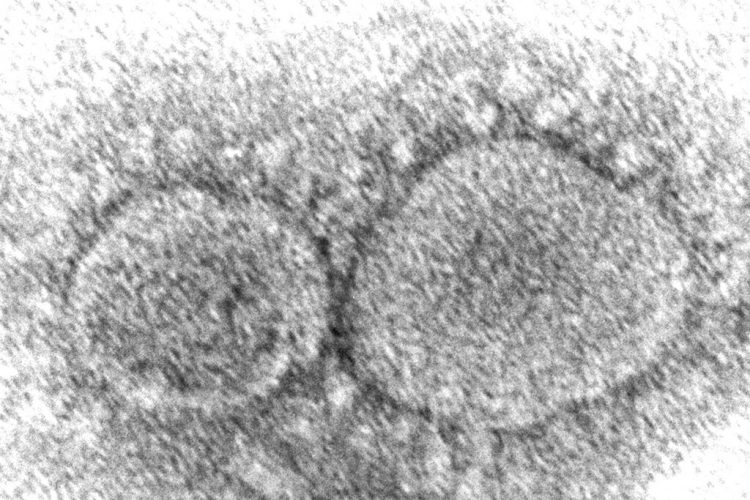

BOSTON (AP) — Boston is planning to establish 11 wastewater testing sites across the city to help monitor for spikes in the COVID-19 virus.

The head of the Boston Public Health Commission said the city is partnering with vendors to create the sites as COVID-19 levels in wastewater across ...